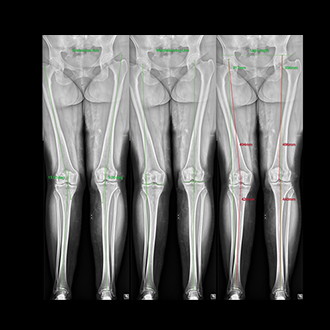

FLFS (Full Leg Full Spine)

This is also called Full Leg Full Spine X-ray system.

This is an integrated system where long segment x-rays of skeletal system are generated.

The x-ray of intended area, viz. whole spine or whole leg are taken together and stitched and printed onto a single film.

This is of great used in pre operative X-rays in certain orthopaedic areas.

We use a dedicated software based measurement system which takes care of most of the needs of orthopaedic surgeon.